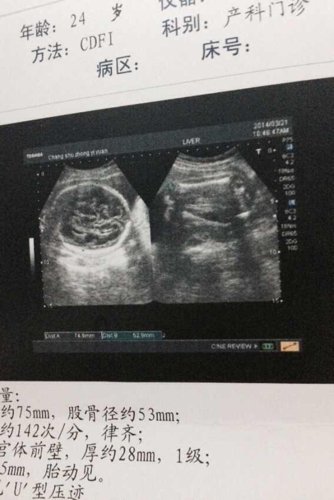

哪位大师能看懂宝宝性别?无所谓男孩女孩,只是好奇

不是动态的画面,又不是自己的手法截取的画面是很难看出性别的,因为你这张多普佳狼勒影像是一吴卫泳种截面图,只有操作者自己操作在动态下才能判断,别人(非操作者)看,只有三维成像后才能判断。【美丽心情】团队,真诚为你解惑,满意请采纳电射哦。